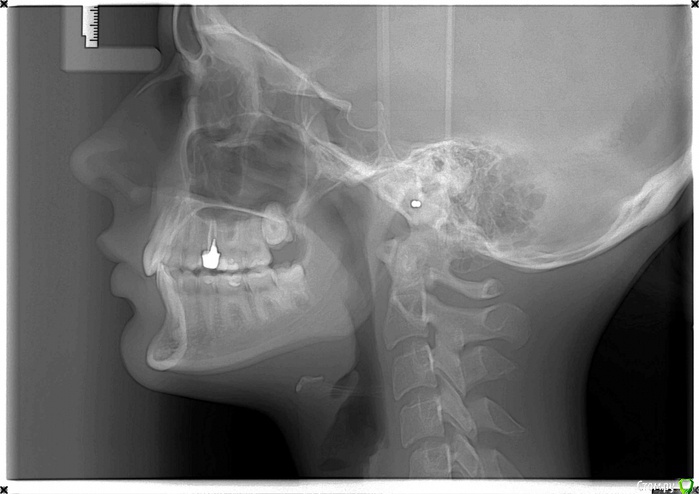

Laaeer Опубликовано 17 сентября, 2015 Поделиться Опубликовано 17 сентября, 2015 (изменено) Добрый день! Несмотря на большое количество подобных тем, хочется открыть и свою, так как, конечно, всё не как у других . Что было до: 24 года, симпатичное лицо с некрасивой улыбкой (зубы наклонены внутрь, глубокий дистальный прикус, сзчла). Небольшая ассиметрия, компенсированный прикус. Щелчки в суставе справа и редкие тянущие слабые боли, стираемость клыка справа и зуба прямо под ним. Эту ситуацию я наивно полагала исправить брекет-системой, ортодонт в ответ на жалобы на щелчки и стираемость сообщил, что щелчки останутся, а стираемость бывает у всех. И вообще был оптимистичен, сказав что ситуация - фигня и нечего особо делать. Брекеты были поставлены (к настоящему моменту я относила их 7 мес), после 6 мес. и выравнивания зубных рядов поставлены самые тугие резинки от нижней семерки к верхней тройке, которые должны были сместить челюсть вперед и вытянуть глубоко посаженные задние зубы. Зубы, только развернувшиеся по красивой дуге стали обратно тянуться в "крысиную улыбку", заворачиваться внутрь. Приношении резинок полностью прошли все боли. С этим я пошла к хирургу. Пластических операций не боюсь, цель - убрать ассиметрию, убрать щелчки, выдвинуть подбородок (улучшить профиль), улучшить эстетику улыбки. Хирург-ортодонт сказал, чтобы я прекратила заниматься ерундой: недоразвитие нижней челюсти брекетами не исправить. Резинки в некоторой степени помогут поднять прикус, но при этом верхние зубы "завернутся", при этом скорее всего хороших контактов зубов добиться не удастся. И все мои время и деньги потрачены, фактически, на небольшой подъем прикуса. Что сустав загружен и работает на износ.Предложенное хирургом лечение: отменить резинки, выровнять до конца зубные ряды, затем хир. выдвижение НЧ, добавление фрагмента на ВЧ (чтобы убрать ассиметрию, кривую улыбку). Потом еще 6 мес брекетов. Это значительно улучшит эстетику и разгрузит сустав. В квалификации хирурга сомневаться не приходится, а в орте есть всё-таки сомнения, но хирургу-то за операции деньги платят так что хочу спросить уважаемых участников форума, кто же из докторов прав? И могут ли быть у такой операции серьезные последствия? Мне она представлена как безопасная, зубы фиксированы брекетами, челюсти - титановыми пластинами, все прогнозируется, всё очень хорошо. (То, что реабилитация тяжелая, я знаю и готова к этому, но вдруг есть какие-то риски, о которых мне не сказали?). Сейчас сняла резинки, беспокоят редкие стреляющие боли в суставе и частые головные боли, начинаются от виска и затем боль распространяется. Боли сильнее, чем до брекетов. Стираемость исчезла. Изменено 17 сентября, 2015 пользователем Laaeer Ссылка на комментарий

Laaeer Опубликовано 17 сентября, 2015 Автор Поделиться Опубликовано 17 сентября, 2015 (изменено) http://img0.liveinternet.ru/images/attach/c/7/125/79/125079440_1175715_mrt.jpghttp://s020.radikal.ru/i700/1509/d1/992519e3c10f.jpg Изменено 17 сентября, 2015 пользователем Laaeer Ссылка на комментарий

Laaeer Опубликовано 7 октября, 2015 Автор Поделиться Опубликовано 7 октября, 2015 (изменено) По результатам осмотра и консультации в Мечникова (были еще и другие, но мнению завкафедры этого заведения нельзя не доверять) буду делать двухчелюстную остеотомию. Глубокий дистальный травмирующий прикус. Работать с суставом будем после нормализации положения и размера челюстей. Еще раз спасибо за комментарии. Если это читает мой хирург - нет, я не жалею, что оббегала пол города и опросила кучу людей, включая этот форум, теперь я могу вам полностью доверять Тему можно закрыть. Изменено 7 октября, 2015 пользователем Laaeer Ссылка на комментарий